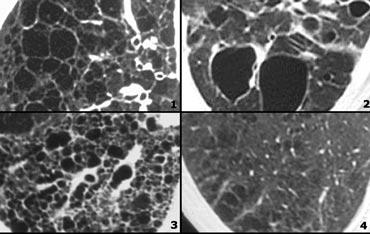

Cystic lung disease

Nang phổi được định nghĩa là các vùng thấu quang với độ dày thành dưới 4mm.

Các bệnh phổi dạng nang được liệt kê trong bảng ở bên trái.

Bên trái là một trường hợp có nhiều nang hình tròn và hình dạng kỳ lạ.

Tổn thương chiếm ưu thế ở thùy trên.

Bệnh nhân có tiền sử hút thuốc lá lâu dài.

Sự kết hợp các dấu hiệu này điển hình cho bệnh mô bào Langerhans.

Bệnh mô bào tế bào Langerhans (LCH) là một bệnh vô căn, đặc trưng ở giai đoạn sớm bởi các nốt u hạt chứa mô bào Langerhans và bạch cầu ái toan.

Ở giai đoạn muộn hơn, các u hạt được thay thế bởi xơ hóa và hình thành các nang.

Đây là một tình trạng không phổ biến.

Phần lớn bệnh nhân là người trẻ hoặc trung niên, biểu hiện với các triệu chứng không đặc hiệu như ho và khó thở. Có đến 20% bệnh nhân biểu hiện bằng tràn khí màng phổi và hơn 90% bệnh nhân là người hút thuốc lá.

Hầu hết các nang có hình tròn, nhưng cũng có thể có hình dạng bất thường (hình thùy đôi hoặc hình lá ba thùy).

Sự chiếm ưu thế ở thùy trên về kích thước và số lượng nang là phổ biến.

Bên trái là một trường hợp có nhiều nang phân bố đều khắp phổi (trái ngược với LCH).

Lưu ý tình trạng tràn khí màng phổi.

Bệnh nhân không có tiền sử hút thuốc và là nữ giới 40 tuổi.

Sự kết hợp các dấu hiệu này điển hình cho Bệnh U Cơ Bạch Huyết (LAM).

Bệnh u cơ bạch huyết là một bệnh hiếm gặp đặc trưng bởi sự tăng sinh tiến triển của các tế bào hình thoi, giống với cơ trơn.

Sự tăng sinh của các tế bào này dọc theo các tiểu phế quản dẫn đến hiện tượng bẫy khí và hình thành các nang phổi thành mỏng.

Vỡ các nang này có thể gây ra tràn khí màng phổi.

Các biểu hiện khác của LAM bao gồm bệnh hạch và tràn dịch màng phổi.

U cơ mạch bạch huyết chỉ xảy ra ở phụ nữ, thường trong độ tuổi sinh đẻ, từ 17 đến 50 tuổi.

Các biến đổi lâm sàng, X-quang và bệnh lý phổi tương tự được thấy ở khoảng 1% bệnh nhân mắc bệnh xơ cứng củ.

Hầu hết bệnh nhân tử vong trong vòng 10 năm kể từ khi khởi phát triệu chứng.